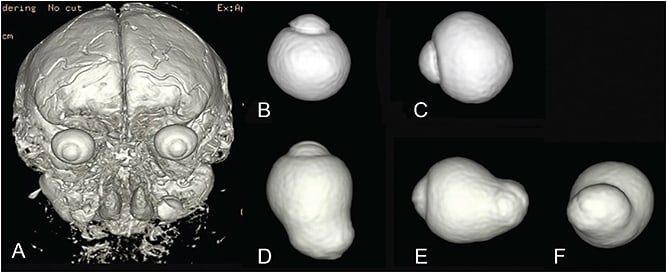

In Pathologic Myopia2 (Figure 1), Spaide clearly defines posterior staphyloma as “an outpouching of the wall of the eye that has a radius of curvature that is less than the surrounding curvature of the wall of the eye.” The author added nasally distorted eye shape to the definition based on results of three-dimensional magnetic resonance imaging (3D MRI) study.4

Staphyloma also can occur in eyes that do not have long axial length. Curtin1 showed that in eyes with type I staphyloma, the most common type, the axial length ranged from 25 mm to 38 mm. He therefore emphasized that axial length was not a reliable marker to define pathologic myopia, and he concluded that pathologic myopia should be defined by the presence of staphyloma. Wang et al6 recently reported clinical features of staphylomas in eyes whose axial lengths measured fewer than 26.5 mm. Thus, outpouching of the wall of eyes without long axial length is also considered to be posterior staphyloma (Figure 1D).

To overcome these problems, Moriyama and the author4,7,8 established a new technique called 3D MRI to analyze the entire shape of the eye (Figure 4). The 3D MRI technique is well suited to examine the eye shape over a wide area that can encompass even a large posterior staphyloma from any angle. The author used 3D MRI and reported posterior outpouching of the globe, suggesting staphyloma was observed in 50.5% of the eyes with mean axial length of 30.0 mm.4 More recently, the author used a combination of 3D MRI and Optos in Japanese and Spanish patients and reported a similar prevalence (55% of the eyes with mean axial length of 30.5 mm).9 These data also showed that even among very long eyes (axial length of 30 mm) about a half of them do not have posterior staphylomas; they were simply elongated in an anteroposterior direction.9

Based on stereoscopic fundus observations, Curtin1 classified posterior staphylomas in eyes with pathologic myopia into 10 types (Figure 6). Types I to V were considered primary staphylomas and types VI to X were combined staphylomas. This is the most frequently used classification; however, it is determined from ophthalmoscopic appearances, which might be rather subjective.

To overcome these issues with Curtin’s classification, the author4 determined the type of staphylomas based on the shape of the entire eye using scans by 3D MRI. To simplify Curtin’s classification, the author analyzed only the contour of the outermost border of staphylomas. This resulted in Curtin types VI to X being placed into the type I category. The staphyloma type is renamed according to its location and distribution; this facilitates with memorization. (Figure 7).

Among staphylomas, the wide macular type was by far the most common (74% of all staphylomas) (Figure 8). The narrow macular type followed (14%) (Figure 9). Other types are rare, and they include inferior staphyloma (3%) and nasal staphyloma (2%).

This detrimental effect might be due to the great expansion of the area of the posterior pole of the eye, as suggested by Spaide.2 As shown in Figure 1, the posterior fundus is stretched even by a simple elongation of the axial length in axial myopia, but the area could not be doubled because the equatorial region mainly elongates and contributes to axial length increase. However, when an outpouching develops, the original area including macula and optic nerve could be greatly expanded and could double. So, it is easy to expect that the mechanical expansion of the occupied area is no comparison between the eyes with and without staphylomas.